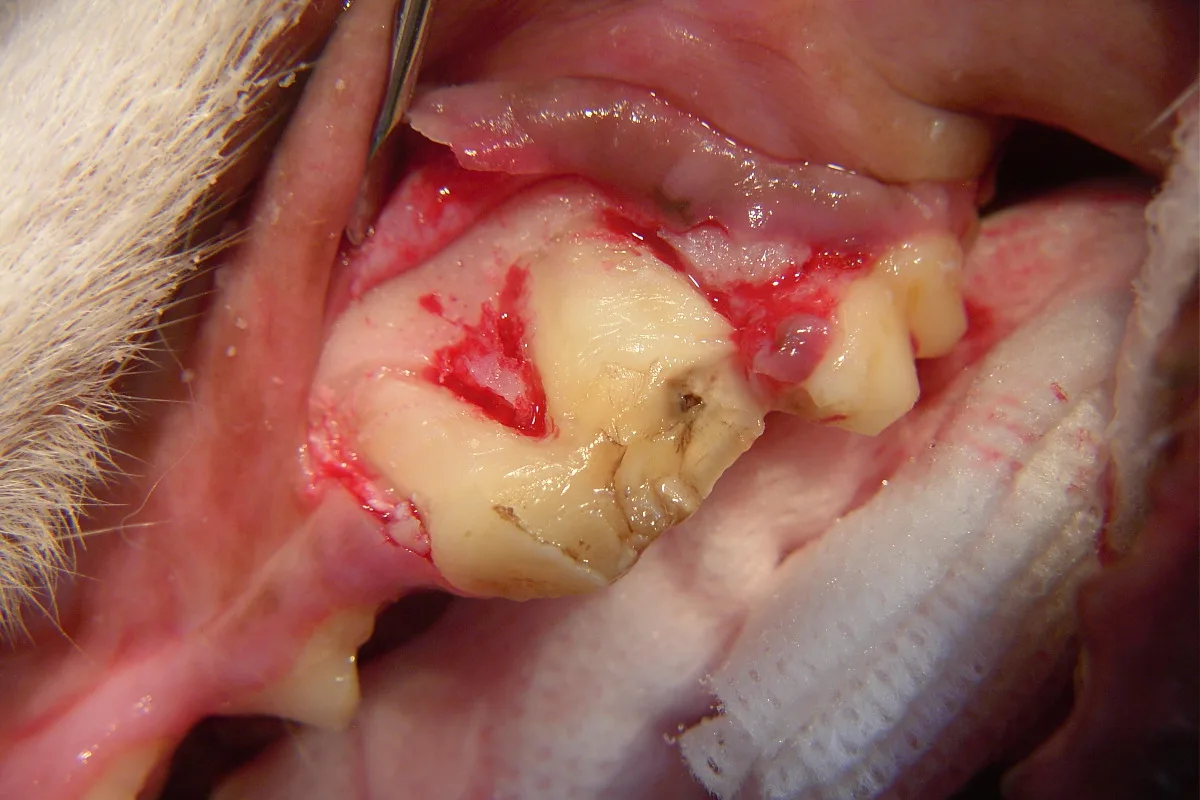

A full thickness mucoperiosteal gingival flap is planned (indicated by the dotted line). Important surgical anatomy includes the parotid and zygomatic salivary ducts at the distal (caudal) aspect of the affected tooth and the infraorbital neurovascular bundle, which is mesial (rostral) to the vertical incision location.

Step 2

The vertical incision is made starting 5 mm apical to the mucogingival line at the mesial aspect of the left maxillary 4th premolar tooth, with firm pressure along the mesial aspect of the alveolar juga of the mesiobuccal root, and continues ventrally to the gingival attachment at the crown. The incision is then extended horizontally within the gingival sulcus, deep enough to reach the alveolar crestal bone, and along the buccal surface of the tooth to the distal aspect of the maxillary 4th premolar. If more surgical exposure of the buccal bone (over the distal root) is needed, the incision can be extended to the distobuccal line angle of the maxillary 1st molar (as is depicted in this and the following steps).5-7 In addition, the remaining epithelial attachment is also incised circumferentially around the maxillary 4th premolar.